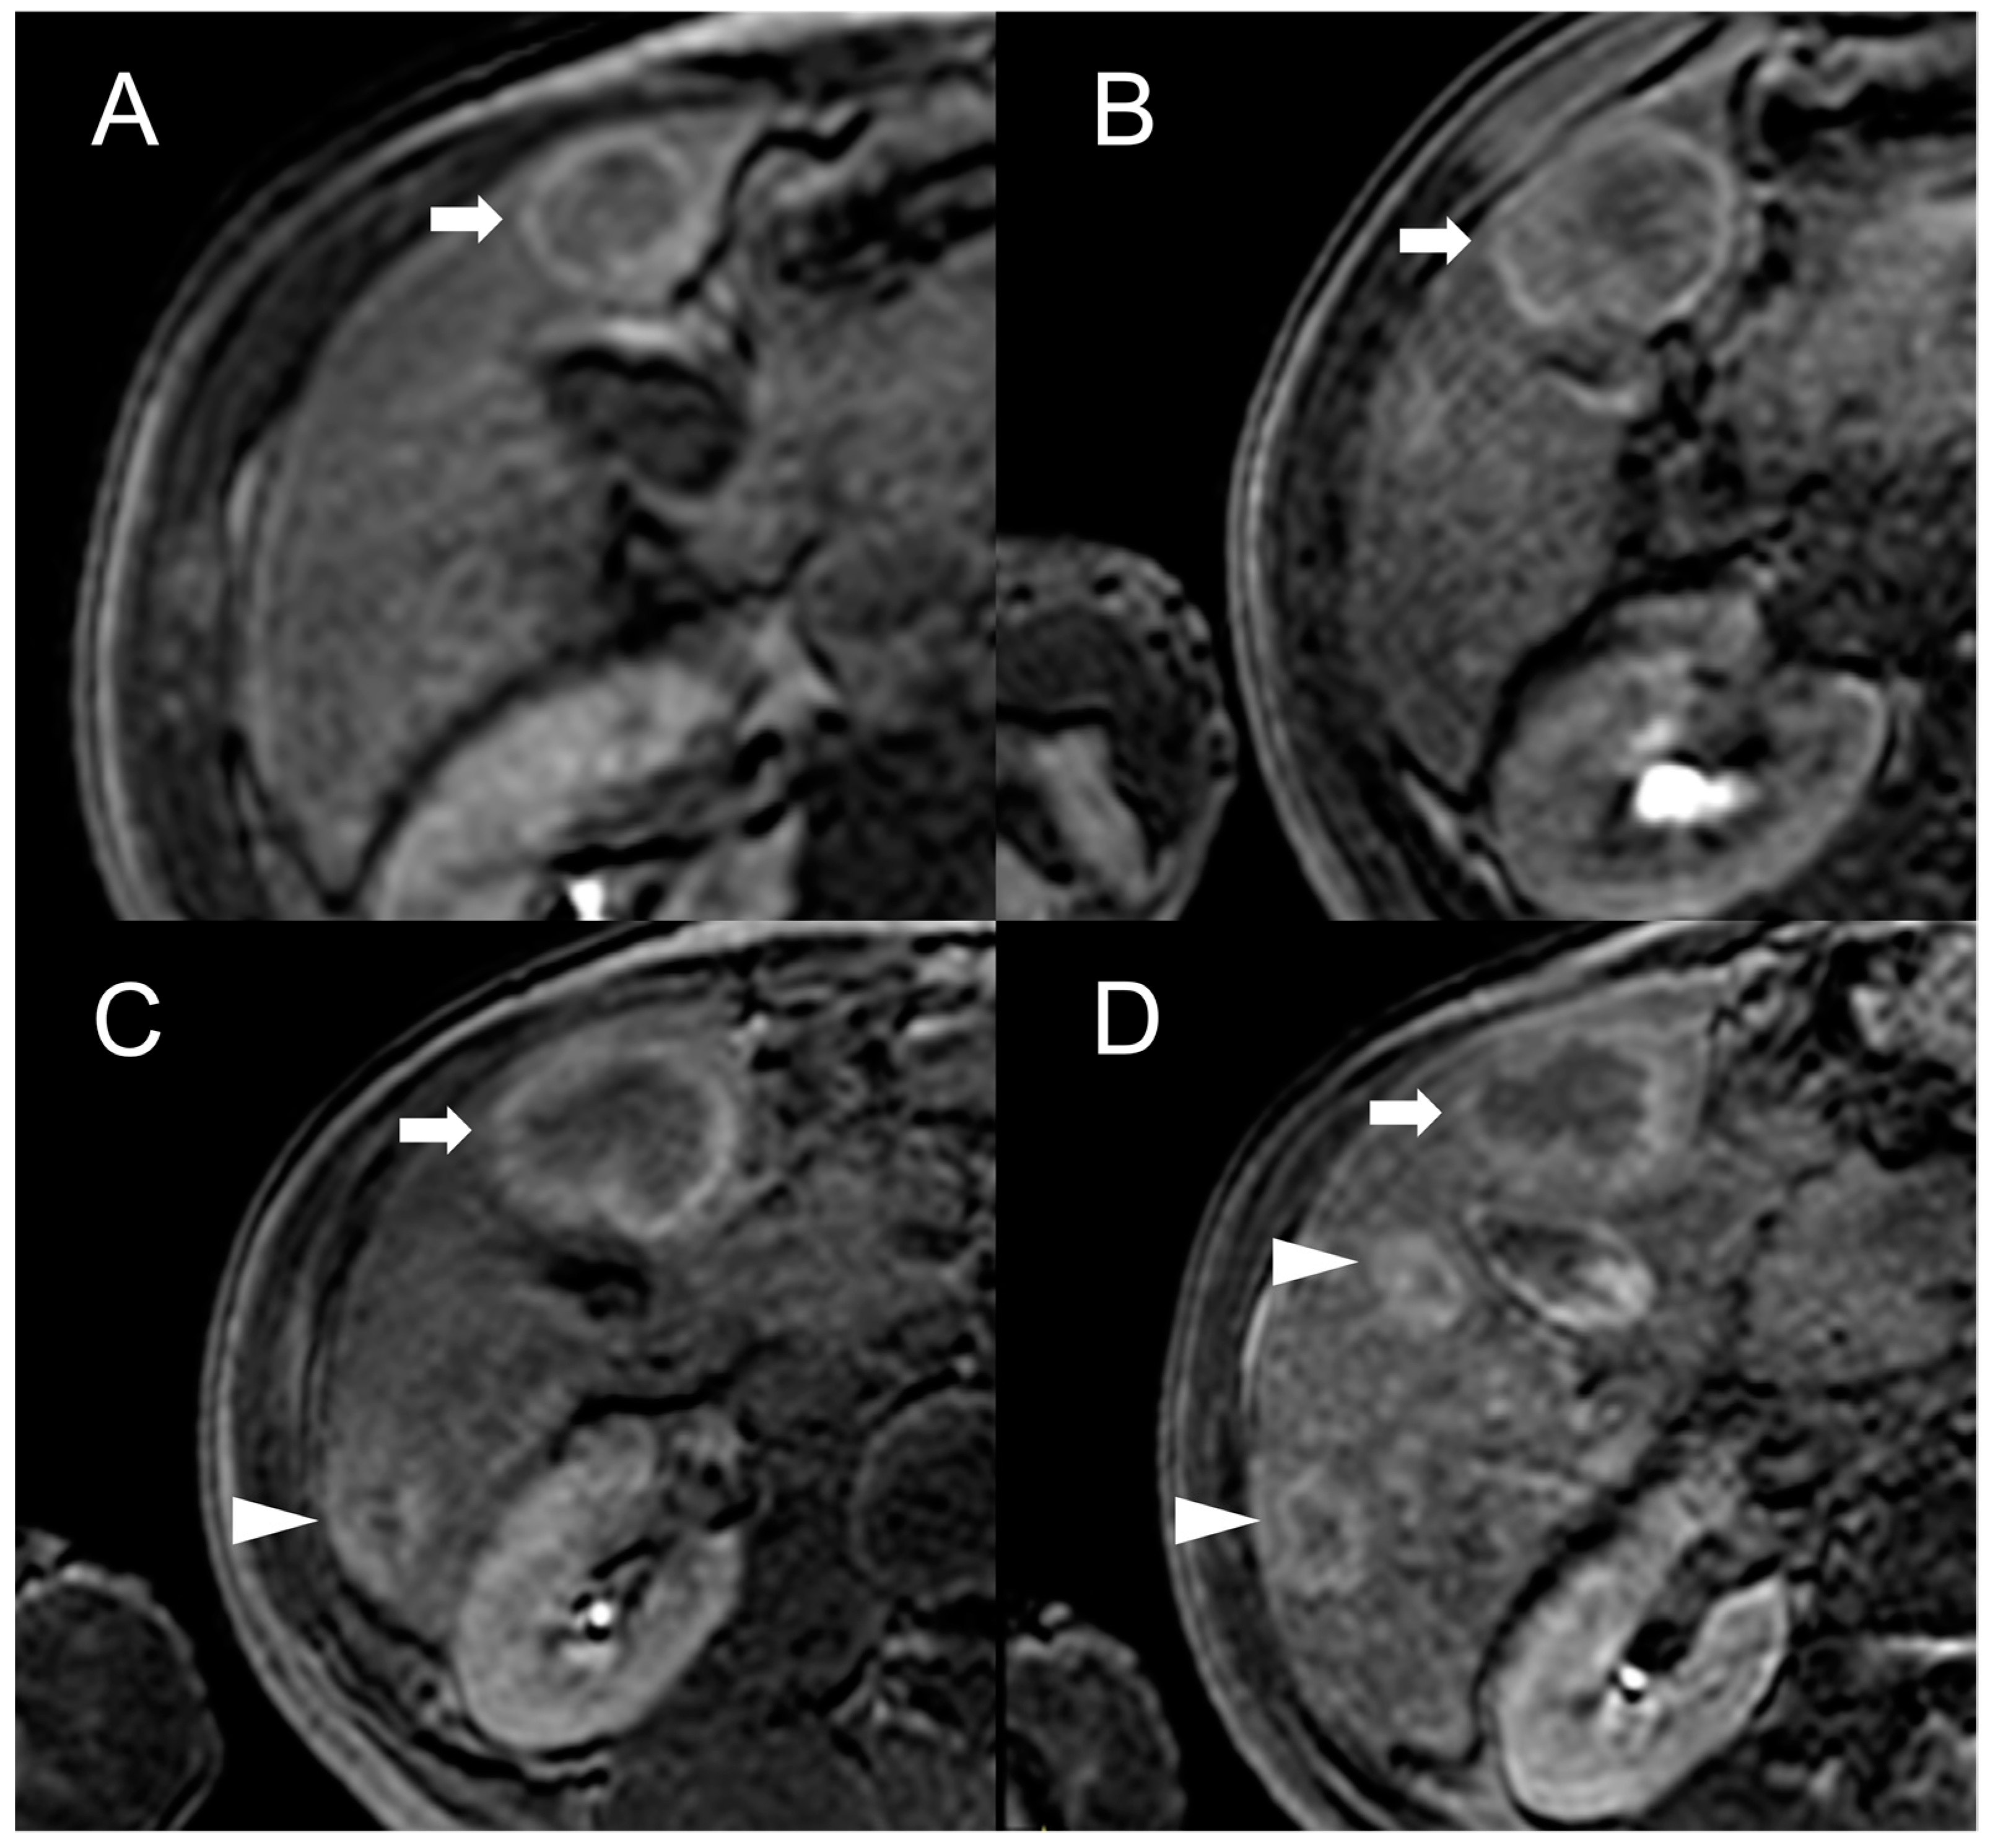

Figure 6.

MRI examination of a 67-year-old female patient with Budd–Chiari syndrome reveals a new focal lesion of 13 mm in the left lobe (arrow). The lesion appears hyperintense on T2-weighted images (A), hypointense on T1-weighted images (B,D) and shows restricted diffusion in high-b-value DWI (C). After contrast agent administration, the lesion demonstrates marked enhancement on T1-weighted arterial phase images (E), followed by central washout with enhancing capsule on T1-weighted portal venous (F) and delayed (G) phases. On T1-weighted images in the hepatobiliary phase (H) the lesion shows a hypointense signal, suggesting a diagnosis of HCC. Perihepatic ascites (asterisks) can be observed on T2-weighted images (A) and DWI (C).

Hepatobiliary contrast agents provide valuable help in the differential diagnosis, as HCC most often demonstrates a hypointense signal in HBP. In the above-mentioned study [22], the combination of this feature with APHE and washout proved effective in distinguishing all HCC lesions from FNH-like RNs. Indeed, benign regenerative lesions typically appear isointense-to-hyperintense compared to the normal liver in HBP, regardless of the presence of washout on portal venous or delayed phase images.

However, considering that approximately 25% of HCCs do not display washout in the portal and delayed phases, while up to one-third of FNH-like RNs can show it, the specificity of this feature for the diagnosis of HCC in BCS is relatively low. As reported by Van Wettere et al. [22], the association of homogeneous APHE and homogeneous washout was identified in one-third of benign lesions and in half of HCC cases. The resulting sensitivity and specificity for diagnosing HCC were 50% and 70%, respectively. When considering the combination of any type of APHE (homogeneous, peripheral or central) and any type of washout (homogeneous or peripheral), a sensitivity of 100% and a specificity of 61% were achieved. For this reason, given the risk of an unacceptable rate of false-positive results, the LI-RADS and AASLD/EASL criteria for the non-invasive diagnosis of HCC cannot be applied in BCS patients [28,29,30]. The differential diagnosis between FNH-like RNs and HCC becomes even more challenging due to the potential for the former to increase in size and/or in number. Therefore, it is important to consider additional features supportive of diagnosis of HCC, such as T1 hypointensity, hyperintensity in T2-weighted and high b-value DWI, and absence of a central scar on MRI [42], as shown in Figure 6.